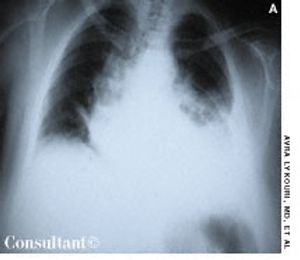

Traumatic hemothorax usually results from penetrating or contused thoracic injuries that lead to rib fracture and damage of intercostal or pulmonary vessels. Hemorrhagic shock can occur with massive blood loss into the pleural space. The shock state may be exacerbated by decreased venous return.